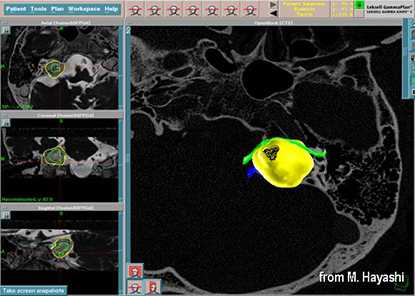

До начала радиохирургического лечения проводится обследование, позволяющее определить точное положение опухоли и прилегающих нервных образований. Выполняется трехмерная реконструкция, отображающая детальную микрохирургическую анатомию этой области. Для этой цели с помощью МРТ получают четкую визуализацию опухоли и нервов во внутреннем слуховом проходе и области мосто-мозжечкового угла.

С помощью планирующей системы Gamma Planи автоматической позиционирующей системывозможно проводить очень точное облучение опухоли (точность 0,5 мм), избегаяповреждения черепных нервов и других важных отделов мозга.